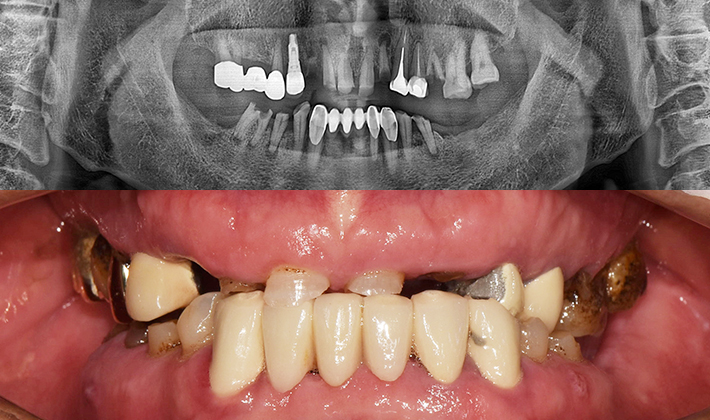

실제 치료 사례

수많은 환자들이 고민 끝에 선택한 치료,

그리고 그 후의 놀라운 변화

- ※ 위 임상사진은 365서울원탑치과에서 진료를 시작하고 마친 동일한 환자의 사진입니다.

- ※ 위 임상사진은 동일한 장소에서 동일한 조건으로 촬영되었으며, 사진에 대한 별도의 조작이 처리되지 않았습니다.

- ※ 수술 및 치료 과정에서 부작용이 발생할 수 있으므로 의료진과의 충분한 상담과 신중한 판단이 요구됩니다.